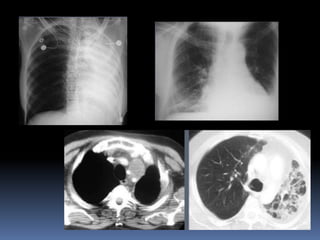

PANAL DE ABEJA  Representa un pulmón destruido y fibrótico que contiene numerosos espacios aéreos quísticos con gruesas paredes fibrosas.  Con pérdida completa de la arquitectura acinar.  Los quistes varían en tamaño desde unos pocos milímetros a varios centímetros de diámetro, tener un espesor de pared variable, y están revestidos por epitelio bronquiolar metaplásico.  RX y TAC :aparece como anillo, típicamente 3-10 mm de diámetro con paredes de 1-3 mm de espesor, que se asemejan a un nido de abeja; el hallazgo implica etapa final de enfermedad pulmonar.  En la TC espacios quísticos aire, diámetros de 3-10 m, ocasionalmente tan grande como 2,5 cm .  Panal suele ser subpleural y se caracteriza por pared definida.  panal de abeja a menudo se considera específico para la fibrosis pulmonar y es una criterio importante en el diagnóstico de neumonía intersticial .

FIBROSIS PULMONAR IDIOPATICA Es una forma específica de fibrosis crónica  se caracteriza por patrón de neumonía intersticial usual.  Radiografías y TAC :  hallazgos típicos de imagen opacidades y panal de abeja, con distribución predominantemente periférica y basal. Opacidad en vidrio esmerilado,